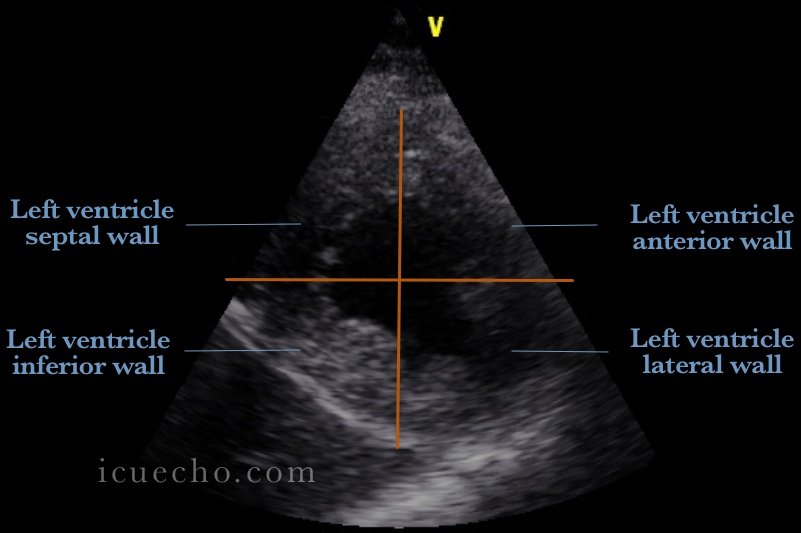

Left ventricular segmentation (PSSA) view: I remember them like: 》In Basal & Mid: ▪︎ Anterior has two arms: Antroseptal & Antrolateral. ▪︎ Inferior has two arms: Inferoseptal & inferolateral. 》Apical: Septal, Anterior, lateral, Inferior. How do you remember them?🤔

Left ventricular segmentation (PSSA) view:

I remember them like:

》In Basal & Mid:

▪︎ Anterior has two arms: Antroseptal & Antrolateral.

▪︎ Inferior has two arms: Inferoseptal & inferolateral.

》Apical: Septal, Anterior, lateral, Inferior.

How do you remember them?🤔